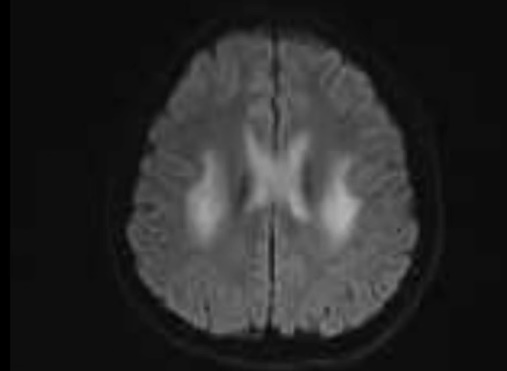

神经内科负责人张冲综合分析患者病史、体格检查、治疗后病情变化及头颅磁共振所示双侧对称性细胞毒性水肿异常信号,考虑患者诊断为可逆性胼胝体压部病变综合征(RESLES-2型)。治疗一周后小甘语言及吞咽功能恢复正常,复查头颅核磁共振可见小甘之前脑内对称性异常信号基本消失。

治疗后